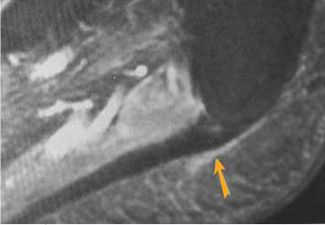

Engrosamiento de la fascia plantar.